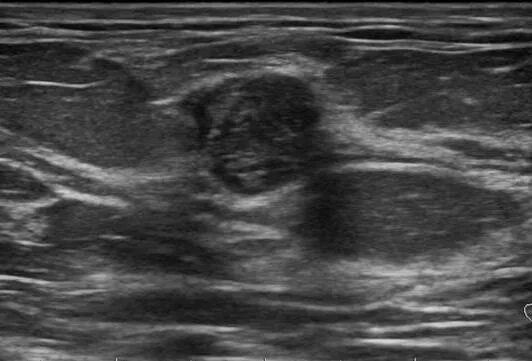

Диффузный аденоз